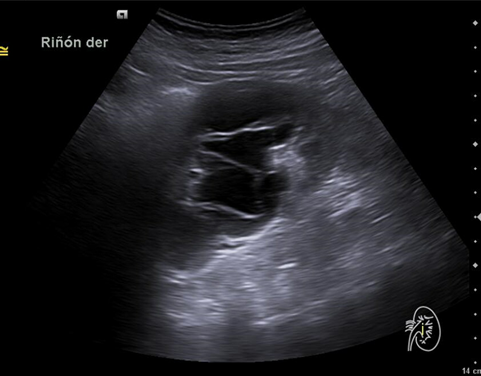

Hallazgos ecográficos

Riñón derecho 9,9 cm con morfología y ecogenicidad conservada. Presenta hidronefrosis grado III. No se identifica causa obstructiva.

Se remite a la paciente a Urgencias donde fue dada de alta con diagnóstico de CRU y tratamiento con Fosfomicina. Consultó al día siguiente, persistiendo el dolor y febrícula, remitiéndose de nuevo a Urgencias. Solicitan estudio de imagen con ecografía y ante los hallazgos se amplió el estudio a TC simple de abdomen: Hidronefrosis grado III con líquido perirrenal sugestivo de rotura de fórnix. Nefrolitiasis puntiformes en ambos cálices inferiores. Sin clara causa obstructiva objetivable. Se contactó con Urología de guardia quien propuso tratamiento ambulatorio con seguimiento posterior y colocación de nefrostomía programas y pielografía para estudio de probable estenosis de unión pieloureteral. Actualmente la paciente permanece en seguimiento por urología.